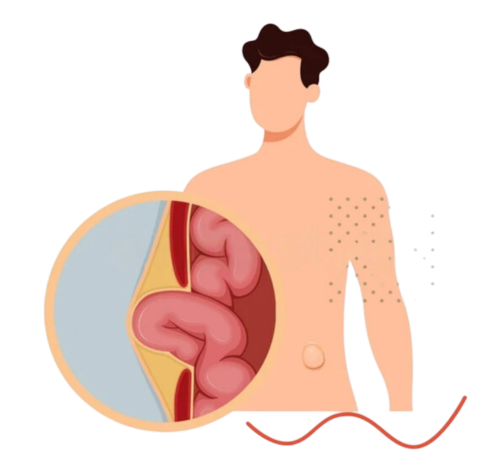

Dr. Lokendra Kumar General and Laparoscopic Surgeon with special interest in Cancer surgery, Gastro ( G.I) surgery and Minimal invasive surgery, More than 14 years of experience in the field expertise in Laparoscopic appendix surgery, Laparoscopic gall bladder surgery, Laparoscopic hernia surgery, Laparoscopic Gastro Surgery, Laparoscopic abdominal surgery, colorectal surgery, thyroid Surgery, varicose veins Surgery, Stone surgery, piles surgery, fistula and fissure Surgery.